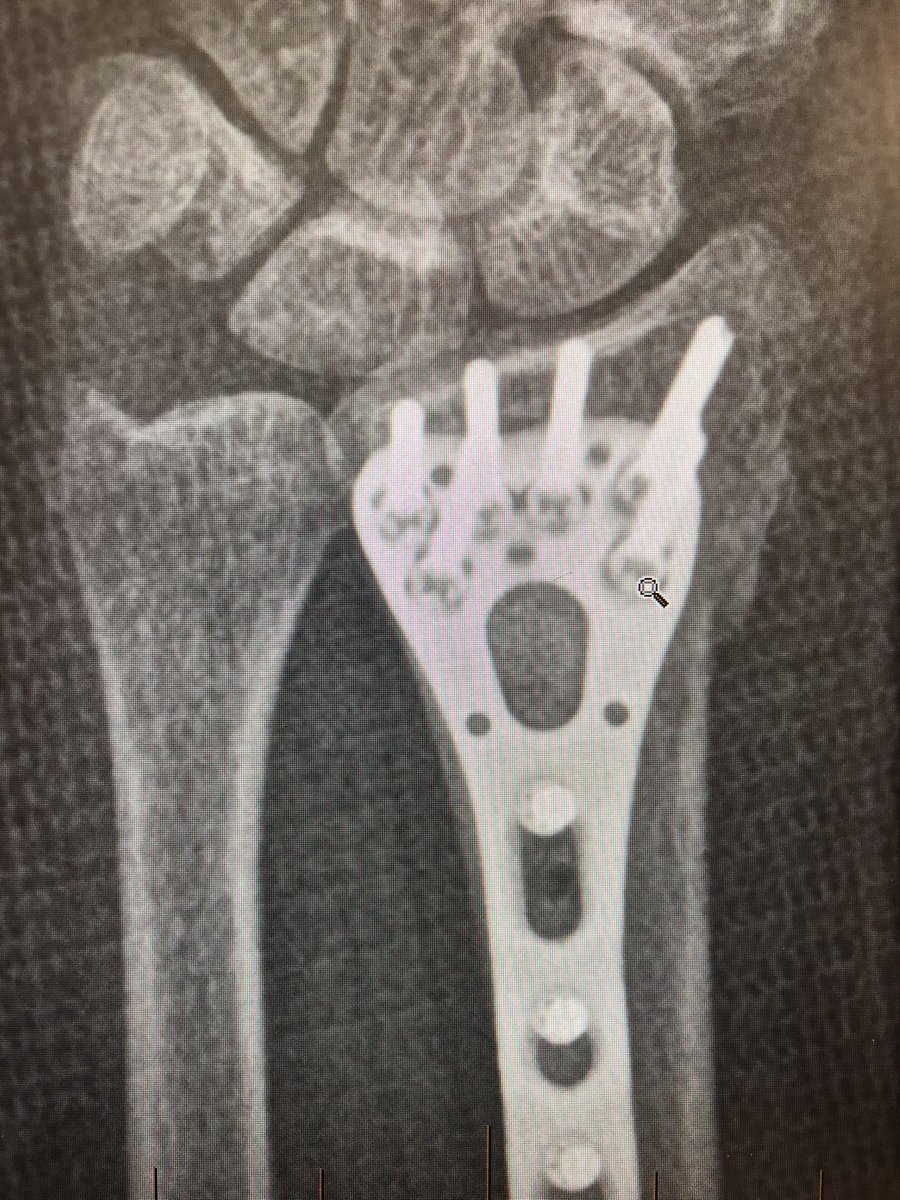

Point 3: the tangential view.

The wrist flexed ‘dorsal tangential view’ or as we locally call it ‘Lleyton Hewitt View’ is increasingly popular (published from our institutes with my colleagues too), but I find the ‘extended tangential’ or ‘DRUJ View’ more informative.

As compared to the dorsal tangential view, this DRUJ view gives better light contrast to view the dorsal rim and also additional information about the DRUJ to make sure there is no screw protrusion into the ulnar notch.